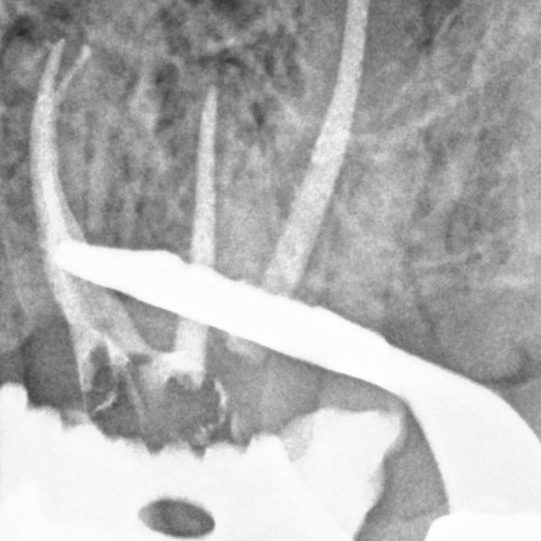

Figure 10: Two cases showing MB2 joining MB1 in the mid-third of the root

- Master cone shows MB2 joining MB1

- MB2 joins MB1 at an acute curvature (white arrow).